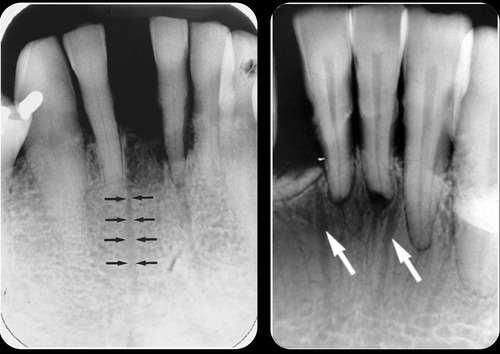

What are nutrient canals?

anatomic structures of the alveolar bone through which neurovascular elements transit

Where are interdental nutrient canals most often seen?

in the anterior mandible, a region that typically has thin bone

Thinning of the nutrient canals is a sign of what?

aging

information on nutrient canals

little lines of radiolucency found in maxillary & mandible

What do nutrient canals look like radiographically?